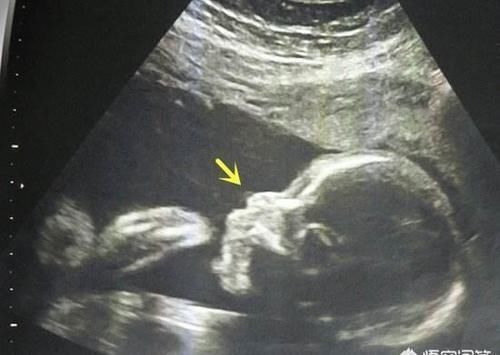

孕23周+2四维显示无鼻骨,虽然孕妈妈的唐氏筛查还有NT的结果都正常,但唐氏筛查的准确率并不高,只有60%左右,孕妈妈还需要去上级医院做更准确的进一步的检查,比如脐带血检查或者是羊水穿刺,准确率都是比较高的。

总之,胎宝宝检查出来没有鼻骨,可能是机器或者角度的问题,但也可能意味着宝宝有染色体方面的异常,所以首先要做的就是排除胎宝宝是否有染色体异常的问题,至于宝宝以后的外貌方面,没有鼻骨不会影响到宝宝的生长发育和外貌,最多只是鼻子有点塌而已,还是可以继续妊娠的。